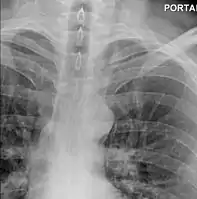

Perforation of the esophagus as seen on esophagogram

The diagnosis of Boerhaave's syndrome is suggested on the plain chest radiography and confirmed by chest CT scan. The initial plain chest radiograph is almost always abnormal in patients with Boerhaave's syndrome and usually reveals mediastinal or free peritoneal air as the initial radiologic manifestation. With cervical esophageal perforations, plain films of the neck show air in the soft tissues of the prevertebral space.

Hours to days later, pleural effusion(s) with or without pneumothorax, widened mediastinum, and subcutaneous emphysema are typically seen. CT scan may show esophageal wall edema and thickening, extraesophageal air, periesophageal fluid with or without gas bubbles, mediastinal widening, and air and fluid in the pleural spaces, retroperitoneum or lesser sac.